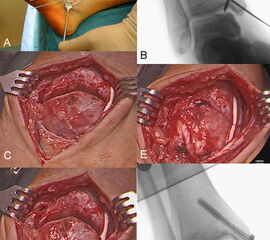

Die Transplantation einzelner osteochondraler Zylinder (OCT) wird für die Behandlung großer zystischer OCLs über 6 mm Durchmesser empfohlen.

Dabei wird die OCL an den Knorpelrändern debridiert, um die echte Größe des Knorpeldefektes zu bestimmen. Anschließend wird dieses Empfängerareal mit der Empfänger-Stanze ausgestanzt. Mit der Spender-Stanze wird der passende Knorpel-Knochen-Zylinder aus einer nicht-lasttragenden Zone (parapatellare Gleitbahn) des ipsilateralen Kniegelenkes gehoben und in die Defektzone eingebracht.

In einer Studie mit 50 durchgeführten OCT-Fällen mit einer Läsionsgröße von 8-20 mm konnte eine 90 %ige Erfolgsrate erreicht werden 99. In einer weiteren Untersuchung an talaren OCLs mit einem follow-up von durchschnittlich 16 Monaten wurde ein postoperativer AOFAS-Score von 88 und ein Lysholm Knie-Score (für die Beurteilung der Entnahmemorbidität) von 97 erreicht. 89 % der Patienten würden das Verfahren erneut wählen 100. Die Autoren empfehlen zudem diese Technik als Rückzugs-Methode für Therapieversager nach z.B. der Mikrofrakturierung oder bei einer langen Symptomdauer einzusetzen.

Die Vitalität der Chondrozyten im Randbereich des Transplantates wird durch Hitzeentwicklung bei der Benutzung von Diamant-Fräsen negativ beeinflusst, sodass für die Gewinnung des Transplantates eher die Verwendung entsprechender Stanzen empfohlen wird, welche mit einem Hammer eingeschlagen werden 101.

Neben der anterograden Technik ist auch die retrograde Implantation für OCLs der postermedialen Talusschulter unter Zuhilfenahme eines CT-basierten Navigationssystems in einer Kadaverstudie beschrieben 102. Dabei wird zunächst ein Zieldraht zentral in der Läsion plaziert, welcher anschließend überbohrt wird, bevor ein entsprechender Spenderzylinder aus dem ipsilateralen Knie eingebracht wird. Die Auswertung nach Osteotomie und mittels CT zeigte eine gute Oberflächenkongruenz und Stabilität. Eine weitere Machbarkeits-Studie an 9 Kadavern konnte die arthroskopische Technik als sicheres Verfahren zur retrograden osteochondralen Zylindertransplantation bestätigen 103.